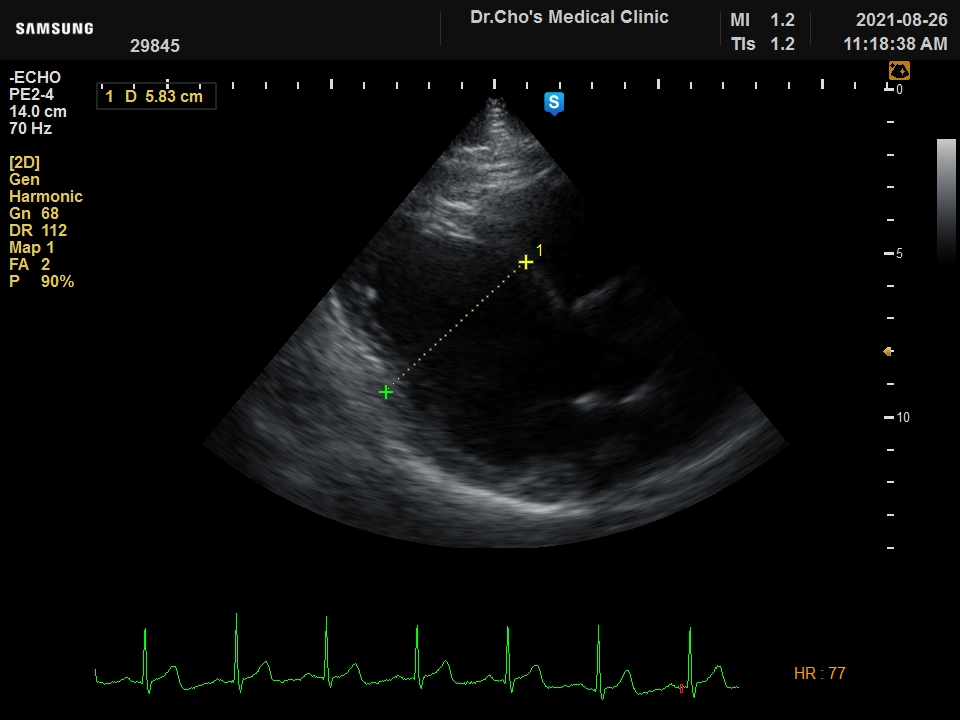

ÃÊÀ½ÆÄ°¶·¯¸®

È®À强 ½É...